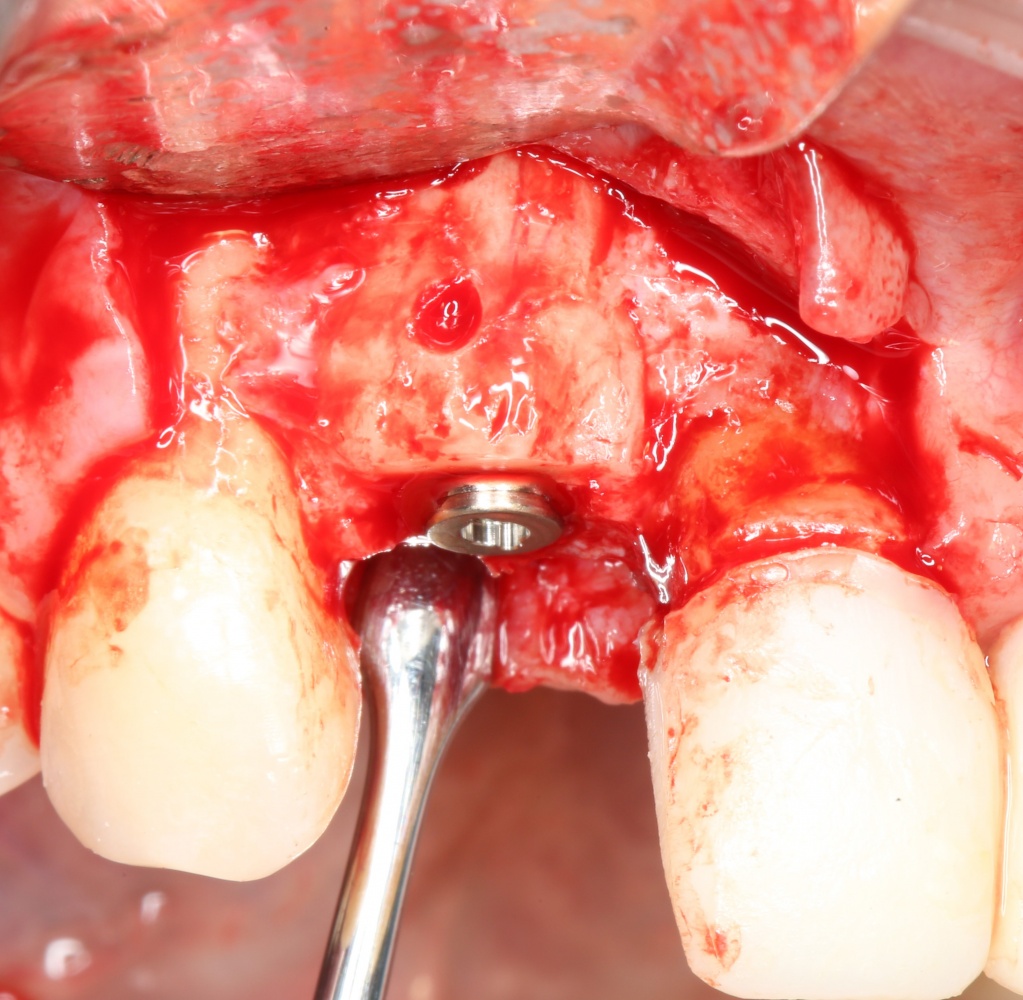

Кстати, обрати внимание на ширину альвеолярного гребня (левая картинка). Она чуть меньше 3 мм. Это объясняет, почему я засомневался в возможности установки имплантатов одновременно с остеопластикой. Понятно и без КЛКТ.

Наперво, мне нужно удалить разрушенный зуб и получить костный аутотрансплантат.

Возвращаемся к основной операционной области. Еще раз посмотрим на альвеолярный гребень, поофигеваем от его ширины и моих грандиозных планов: